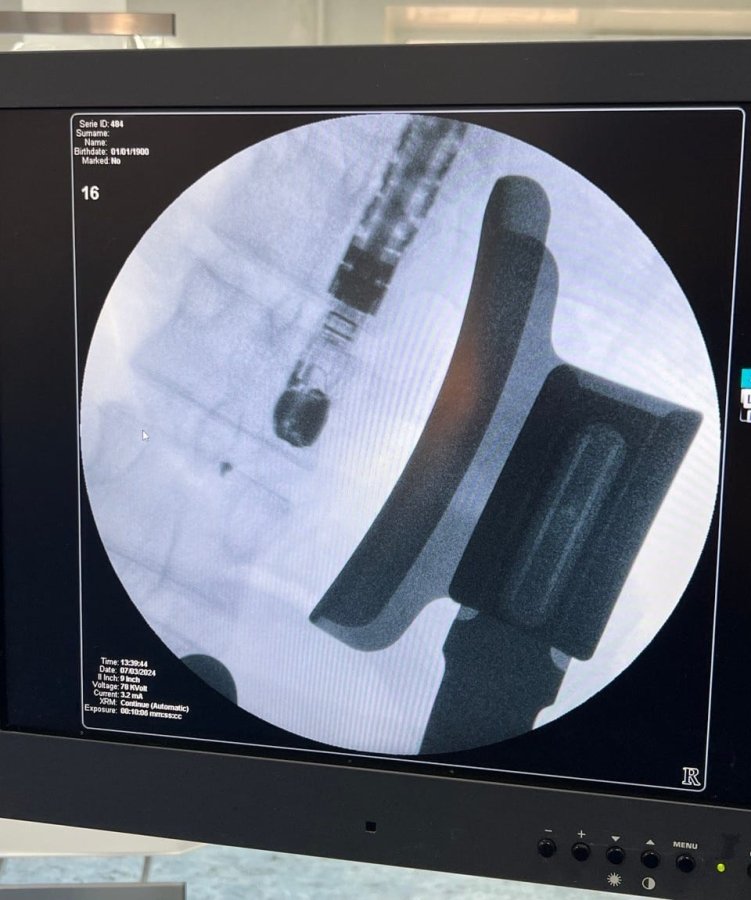

Вінницька обласна клінічна лікарня імені М. І. Пирогова повідомила, що 22-річний пацієнт зазнав проникаючої травми грудної клітини. Діагностичні процедури виявили два чужорідні тіла - металеві фрагменти у стінці правого шлуночка серця.

«7 березня, використовуючи гібридну операційну залу лікарні, було здійснено високотехнологічне хірургічне втручання без зупинки серця та кровообігу через мінімальний доступ - міні j-стернотомію. Операція включала використання передових методів рентгеннавігації та магнітних інструментів», - зазначається у звіті лікарні.